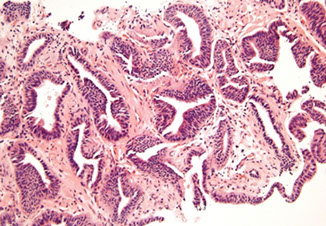

Ductal Adenocarcinoma

Hard to diff HG-PIN and ductal AC

- ductal ACs are agressive, advanced stage, and assoc c a poor px

- critical to diff from PIN

- ductal AC usually centrally located in periurethral region and sampled on TURP

-- PIN uncommon in periurethral region and infreq seen on TURP

- ductal AC usually has true papillary fronds c well-formed fibrovascular core, whereas HG-PIN more freq reveals micropapillary fronds c tall columns of epithelium w/o fibrovascular stalks

- ductal AC freq has comedonecrosis, which can be extensive

-- HG-PIN lacks comedonecrosis

- ductal AC can consist of large or back-to-back glands, whereas glands c PIN are of the size and distribution of b9 glands

- use of basal cell markers in the DDx can be problematic as both HG-PIN and ductal AC can have a patchy basal cell layer, however, the lack of a basal cell layer in numerous glands rules out PIN

Although the MC forms of ductal AC mimic cribriform and micropapillary HG-PIN, ductal AC can be composed of simple glands lined by stratified columnar epithelium c cytologic and architectural features of flat and tufting HG-PIN

- these PIN-like ductal cancers are distinguished from HG-PIN either bc the atypical glands are too crowded to represent HG-PIN or there are too many atypical glands that are negative for basal cell markers to be consistent with HG-PIN

- additional differences are in the PIN-like ductal AC, many of the glands are lined by flat epithelium (an uncommon pattern in HG-PIN) and the glands are often cystically dilated

Px: up to 1/2 metastatic at dx